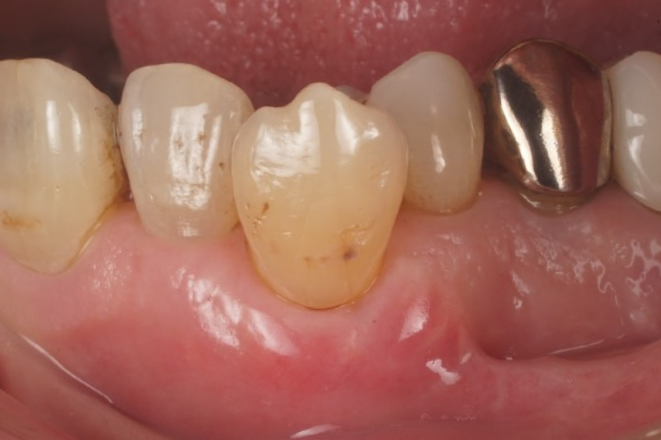

症例3

| 項目 | 詳細 |

|---|---|

| 患者様データ | 40代 男性 |

| 来院時の主訴 | 「前歯を歯磨きすると痛いし、出血する。」 |

| 医院の診断 | 右上中切歯根尖性歯周炎、歯周病 |

| 通院期間 |

6か月 |

| 来院回数 | 10回 |

| 治療費 | 総額:歯周病治療に関しては保険適用診療。その他:370,000円(税抜) 【内訳】 歯周病治療(歯周病検査・歯磨きや生活習慣指導・歯石取りクリーニング) その他、精密根管治療 70,000円、ファイバーポストコア 20,000円、セラミック治療 140,000円×2 |

| リスクと副作用 | メインテナンスが必要、正しい歯磨き習慣が必要不可欠 |

| ここがこだわりのポイント!☝ | こちらは中等度の歯周病と虫歯を併発されていた患者様です。日々の歯磨き習慣を見直していただき、正しいブラッシング法を身につけたことで健康な歯肉を取り戻しました!短期間での治療を希望されていたので審美的な歯肉ラインの獲得はできませんでしたが、健康的な歯肉を獲得できました。 |